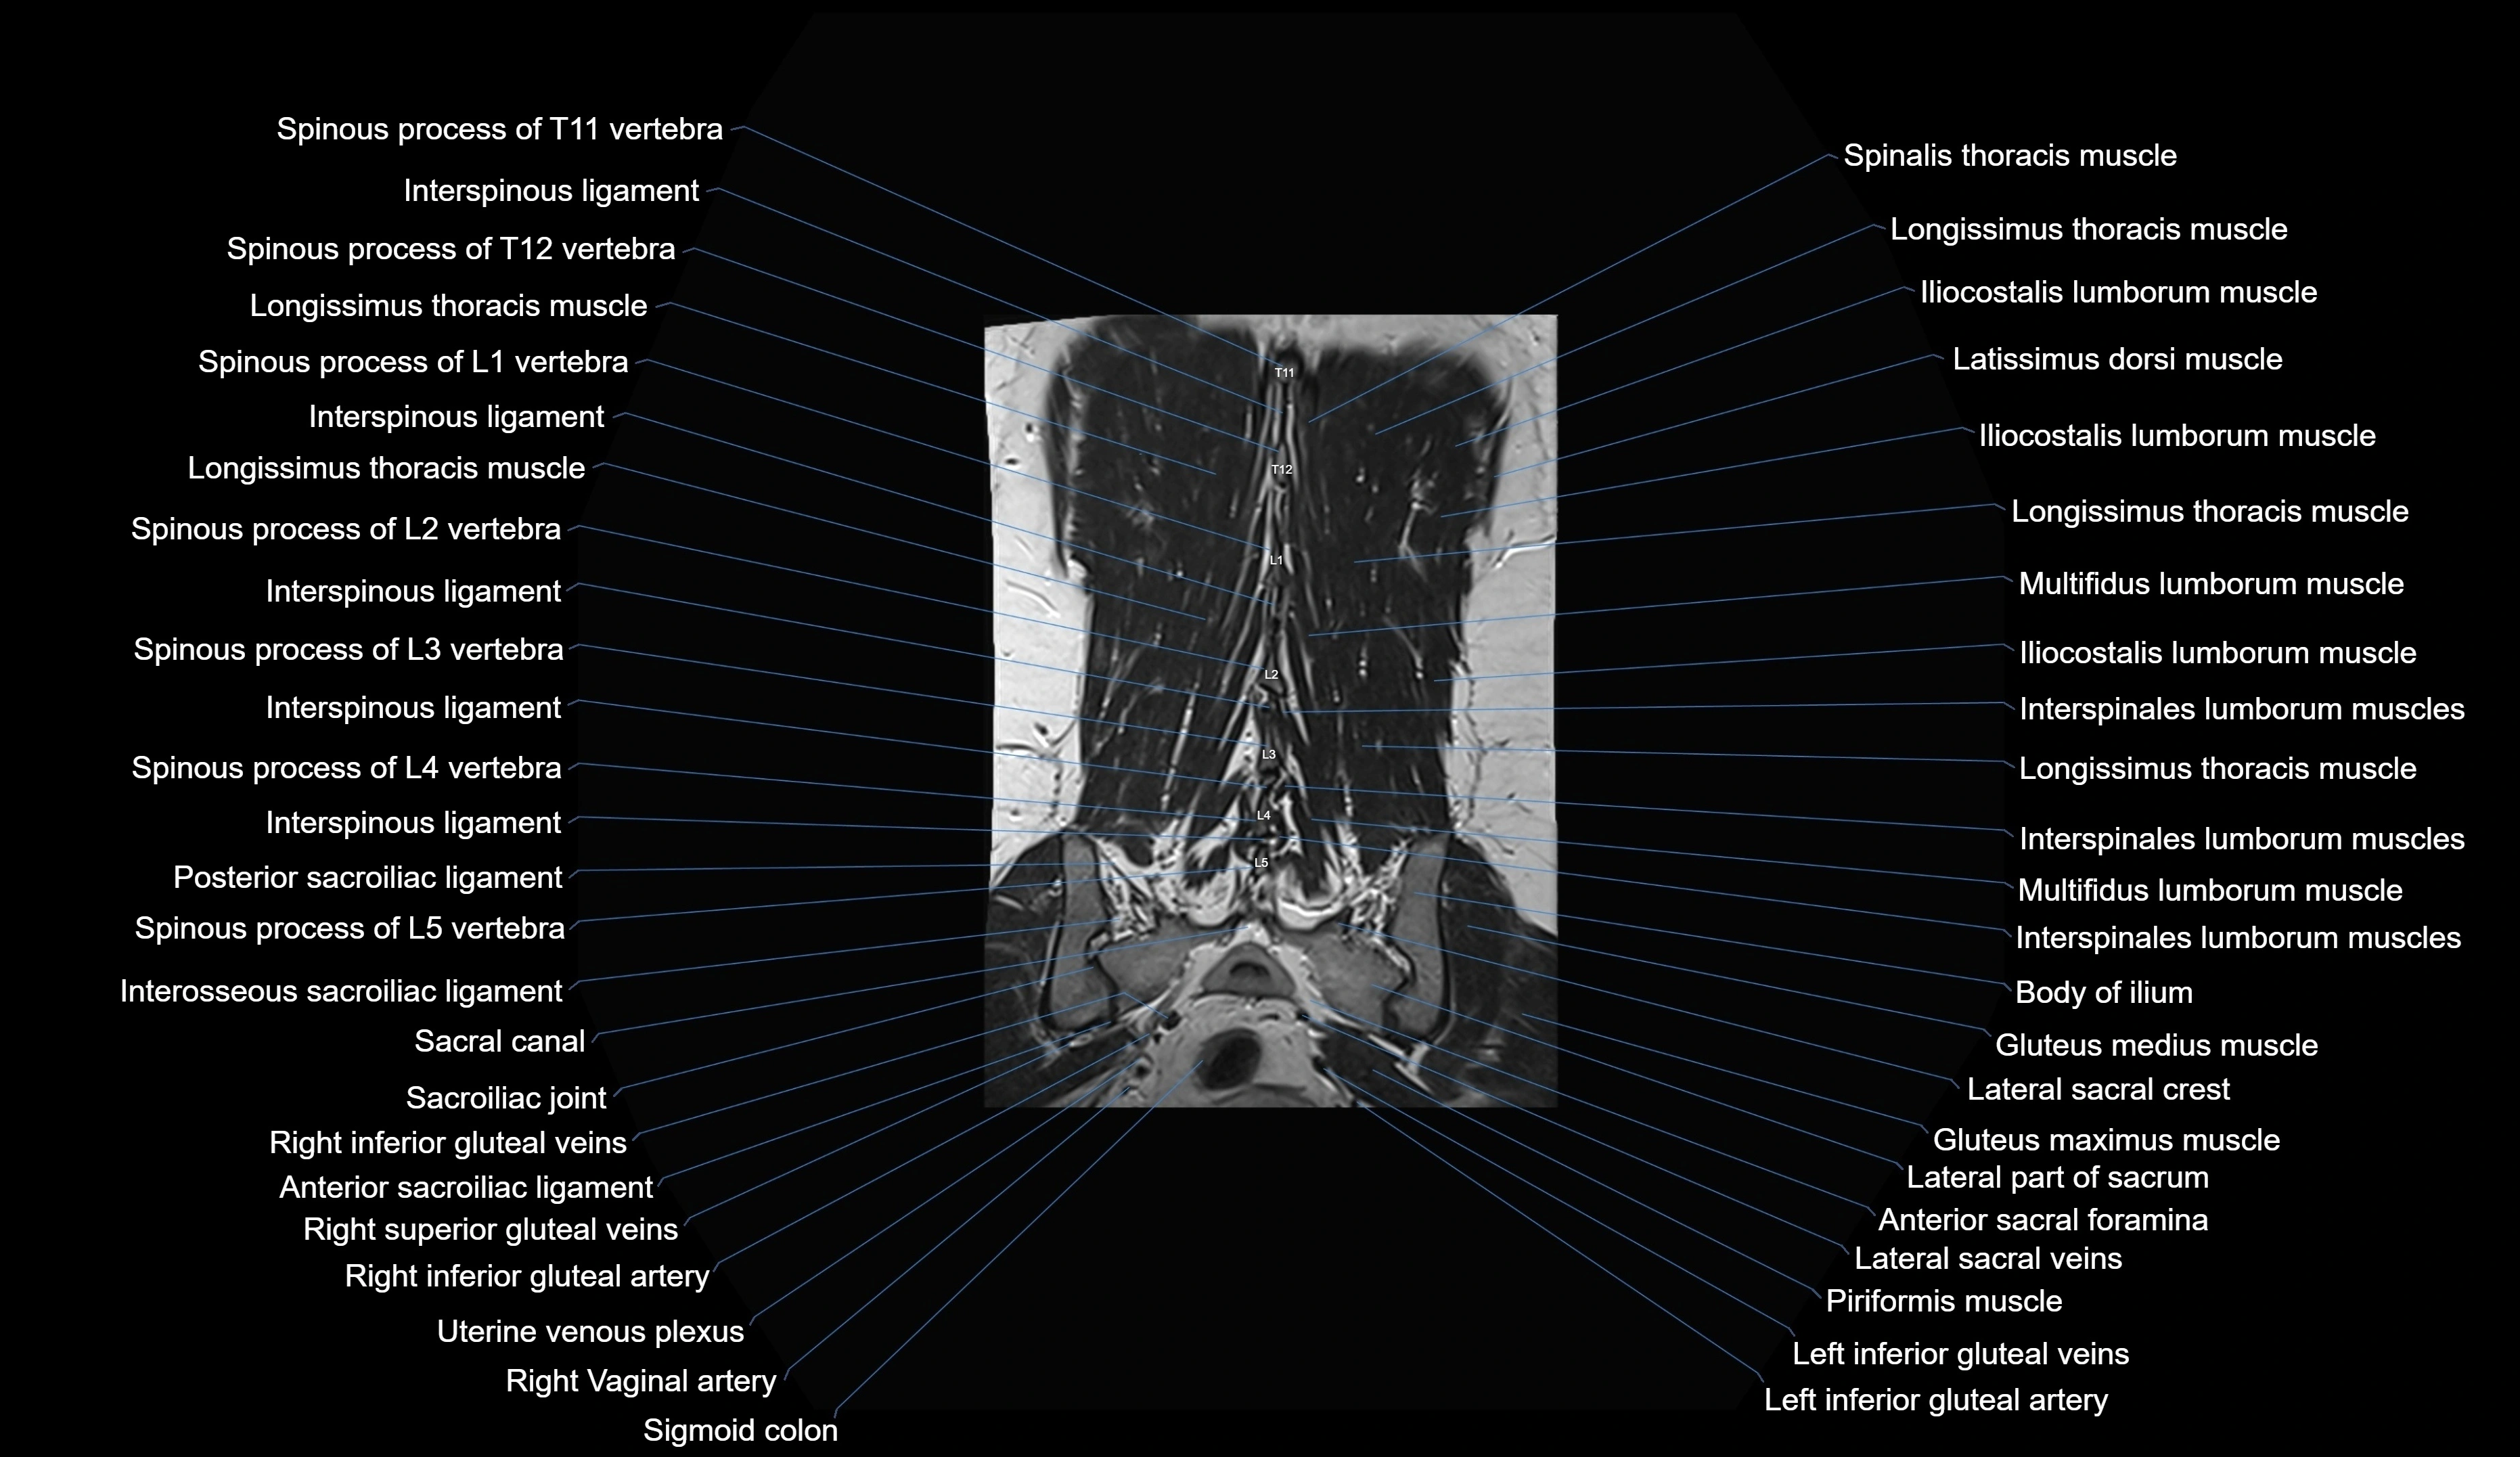

MRI images